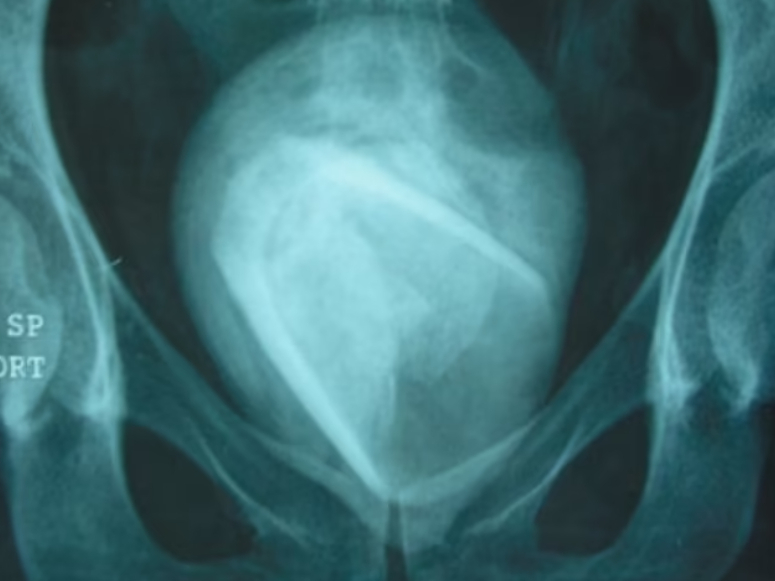

Det afslørede, at kvindens krop kæmpede mod en eller anden form for fremmedlegeme, og scanninger afslørede, at kvinden havde en “gigantisk” og “rektangulær” blæresten på 8x7x8 centimer inde i sig.

En normal blæresten er et sted mellem så lille, at man ikke kan se det med det menneskelige øje til maksimalt et par centimeter, og lægerne vidste derfor, at der var noget helt galt.

De fandt hurtigt ud af, at blærestenen var opstået, fordi den tilsyneladende ‘voksede’ rundt om et fremmedobjekt, som befandt sig i kvindens blære, og som senere viste sig at være et drikkeglas, som kvinden havde ‘mistet’ deroppe for cirka fire år siden, da hun havde forsøgt at bruge det i forbindelse med et “erotisk ærinde.”